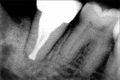

Successful endodontic treatment relies upon a thorough knowledge of root canal anatomical variations along with proper diagnosis, treatment planning, and clinical expertise. One of the difficult root canal configurations that are frequently encountered commonly in mandibular second molars is C-shaped root canal. Due to the intricate root canal configuration, it is often difficult to negotiate, debride, and obturate such canals leading to failure of root canal treatment. Understanding the anatomical variation and adequate visualization will enable the clinician to manage these cases effectively. Advanced irrigation and obturation techniques help in managing such anomalous canal configurations. This article presents the management of two different C-shaped root canal configurations under dental operating microscope using thermoplasticized obturation techniques.